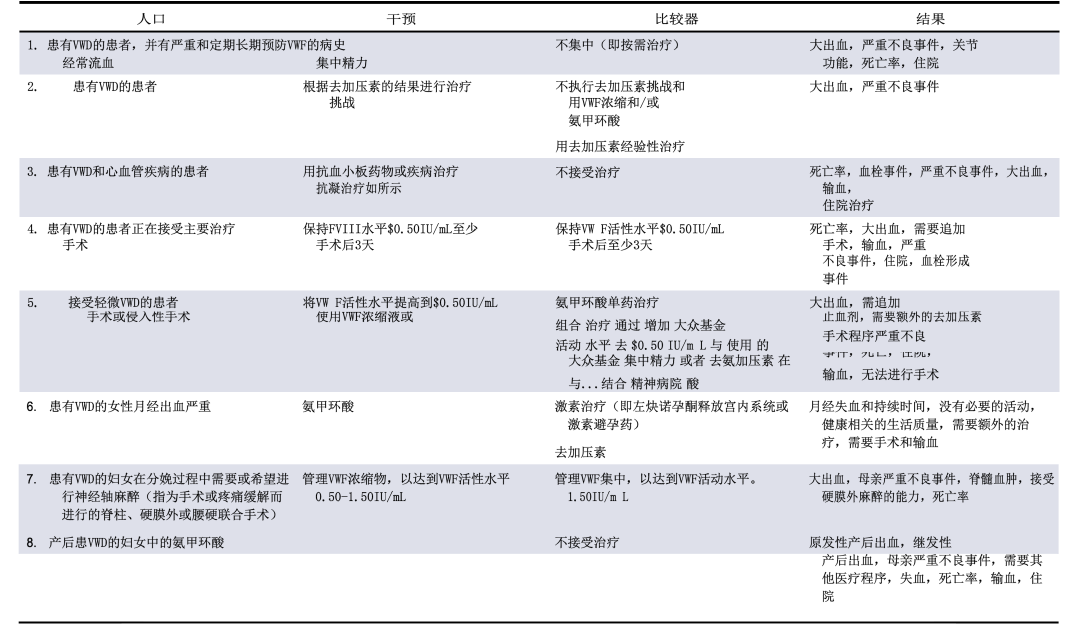

2021年1月,美国血液病学会(ASH)联合国际血栓与止血学会(ISTH)、国家血友病基金会(NHF)以及世界血友病联盟(WFH)共同发布了血管性血友病的治疗指南...